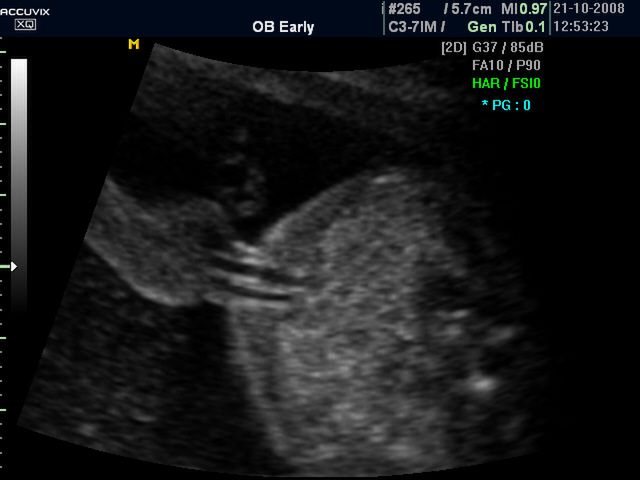

/ 10Zdjęcia płodu - męskie narządy płciowe

Płód w 32 tygodniu ciąży, na zdjęciu widoczne męskie narządy płciowe